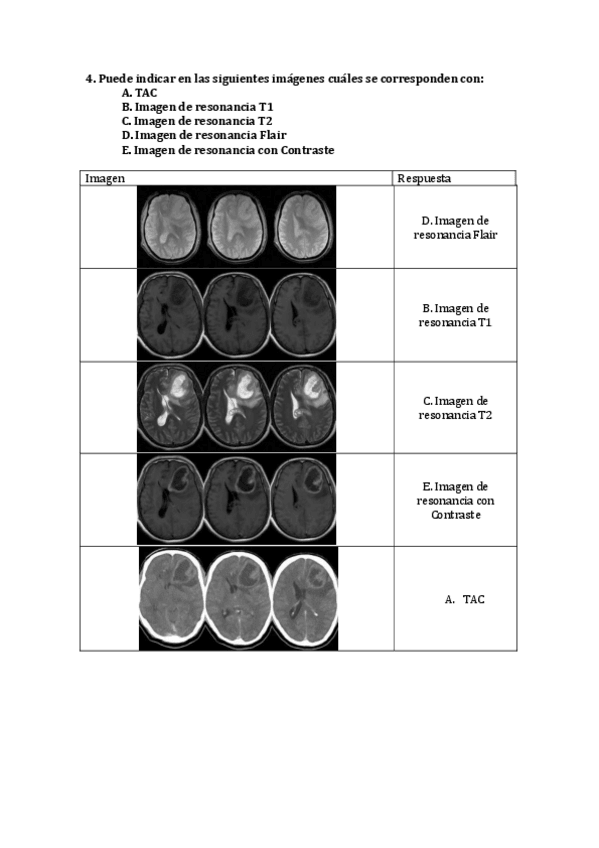

He publicado nuevos apuntes de 4º Neuropsicología Clínica: Tarea-Neuroimagen.pdf

3 páginas

He publicado nuevos apuntes de 4º Neuropsicología Clínica: Tarea-Neuroimagen-.pdf

He publicado nuevos trabajos de 4º Neuropsicología Clínica: Tarea-Neuroimagen.pdf

Tarea-Neuroimagen.pdf